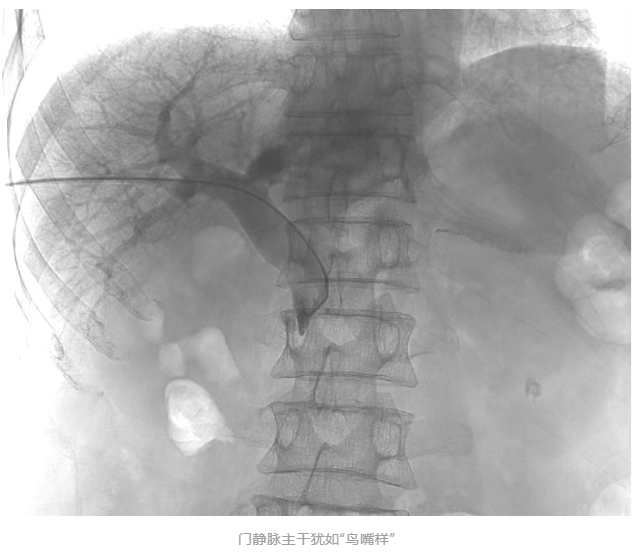

胡育斌主任医师团队在方主亭副院长的指导下开展手术。术中造影显示:肠系膜上静脉完全闭塞,门静脉主干受肿瘤压迫呈“鸟嘴样”狭窄(见下图),血流近乎中断,情况极为严峻。